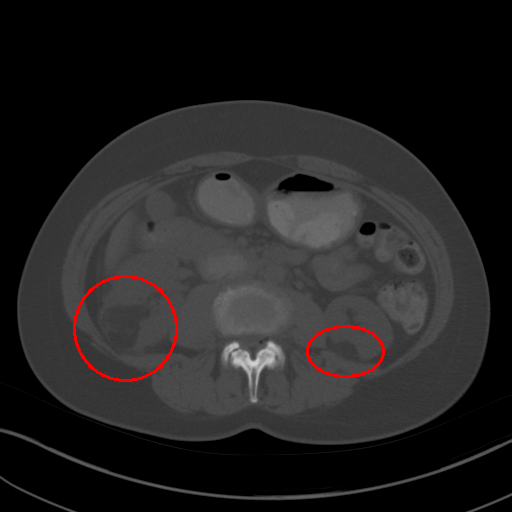

(c) [-505, 1980]

Figure 1: CT images under different window level and window width. (a) is the image used in 3DCE. (b),(c),(d) are the multi-view images used in our MVP-Net.

To accommodate for network input, previous studies [5, 6] use a significantly wide window222Windowing, also known as gray-level mapping, is used to change the appearance of the picture to highlight particular structures. to compress CT’s 12bit Hounsfield Uint (HU). However, this would severely deteriorate the visibility of lesions as a result of degenerated image contrast, as shown in Fig.1(a). In the clinical practice, fusing information from multiple windows are effective in improving the accuracy of detecting subtle lesions and reducing false positives (FPs). During visual inspection of the CT images, radiologists would combine complex information of different inner structures and tissues from multiple reconstructions under different window widths and window levels to locate possible lesions. To imitate this process, we propose to extract prominent features from three frequently examined window widths and window levels and capture complementary information across different windows with an attention based feature aggregation module.

The multi-view input for the MVP-Net is composed of multiple reconstructions under different window widths and window levels. Specifically, we adopt k-means algorithm to cluster the recommended windows (labeled by radiologists) in the DeepLesion dataset and obtain three most frequently inspected windows, whose window levels and window widths are [50,449]50449[50,449], [505,1980]5051980[-505,1980] and [446,1960]4461960[446,1960] respectively. As shown in Fig.1, these clustered windows approximately correspond to the soft-tissue window, lung window, and the union of bone, brain, and mediastinal windows respectively.

We also perform a case study to analyze the importance of multi-view modeling. As shown in Fig. 3, the model indeed benefits from the multi-view modeling: the lesions that are originally indistinguishable in the view of 3DCE due to the wide window range and lack of contrast, now becomes distinguishable under the view of appropriate windows. Thus our model presents better identification and localization performance.